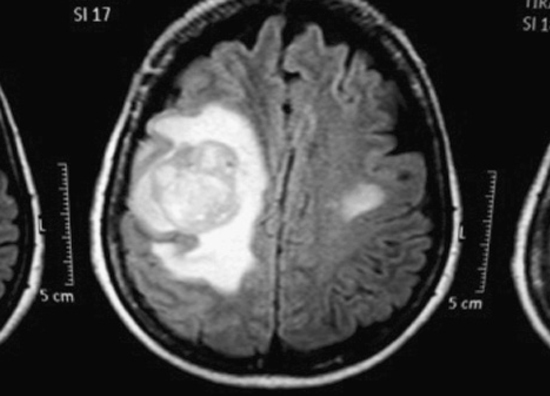

Se controló en octubre 2008 con TSH: 0,3 uU/mL; Tg: 50,5 ng/mL; Ac Tg: 159 IU/ml. Una ecografía cervical en Diciembre 2008 mostró 2 nódulos hipoecogénicos derechos, vascularizados, de 14 mm, con aspecto de adenopatías. La biopsia con aguja fina de una adenopatía reveló metástasis de carcinoma folicular tiroideo con tiroglobulina en la adenopatía > 300 ng/mL. Un nuevo TAC de tórax evidenció aumento en número y tamaño de las lesiones pulmonares. En abril 2009, previa marcación con azul de metileno, se realiza resección selectiva de adenopatía derecha cuya biopsia resultó "metástasis de carcinoma folicular tiroideo" planificándose nueva dosis de I131 que no se alcanza a dar por cuadro de 3 días de evolución de hemiparesia faciobraquiocrural izquierda. TAC de cerebro reveló masa compatible con metástasis cerebral parietal derecha, con edema perilesional y una segunda lesión sospechosa de ser otra metástasis. Además de la levotiroxina, se indicó dexametasona, fenitoina. La RNde cerebro informó: "Proceso expansivo frontal derecho de predominio subcortical, bien delimitado, heterogéneo, con intenso realce tras la administración de contraste, lo que determina efecto de masa sobre el parénquima adyacente. Mide 47 mm. Existe un segundo proceso expansivo en región precentral izquierda de 8 mm. Pequeños focos de incremento de señal en la sustancia blanca subcortical bifrontal. Conclusión: Múltiples lesiones con aspecto de implantes secundarios frontales bilaterales y occipital izquierdo" (Figura 1).

Figura 1. RN que muestra metástasis cerebrales.